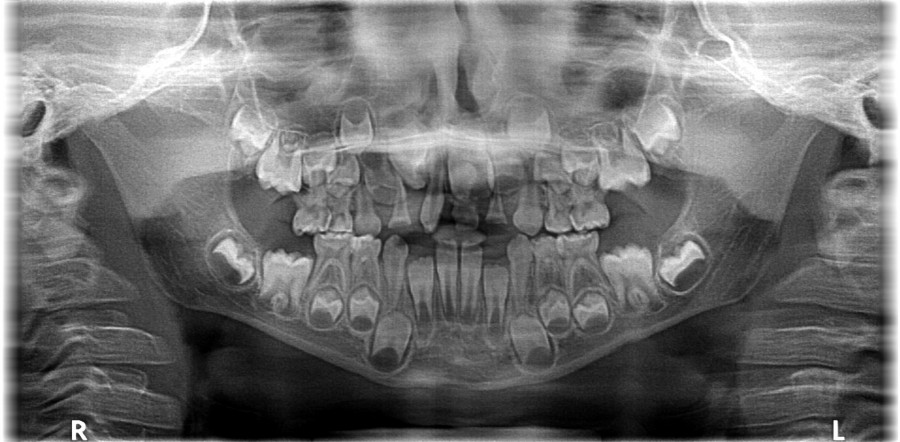

Chłopczyk w wieku 5,5 lat został skierowany przez ortodontę do placówki Stomatologia Bez Bólu z Jeleniej Góry w celu konsultacji i leczenia zaburzenia w okolicy zębów centralnych. Anomalia została wykryta na podstawie zdjęcia pantomograficznego, standardowo wykonywanego przed leczeniem ortodontycznym.

Po badaniu wewnątrzustnym stwierdzono uzębienie mieszane, adekwatne do wieku rozwojowego, bez czynnych ognisk próchnicowych. Zlecono badanie CBCT w celu dokładniejszej diagnostyki lokalizacji i liczebności przednich zębów w szczęce. W obrazie tomograficznym ukazał się od strony szczytu wyrostka, położony ząb nadliczbowy (mesiodens). Mezjodens w tym przypadku zajął miejsce stałego siekacza prawego, powodując jego dystorotacje. Usunięcia mezjodensa umożliwi wyrzniecie się zęba stałego we właściwej pozycji nie wykluczone jest wspomaganie ortodontyczne w celu ustanowieniu właściwej lokalizacji stałego zęba siecznego.